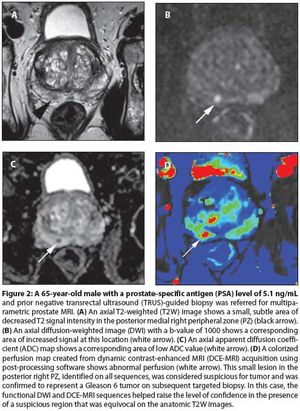

Our aims in this article are to describe the various imaging sequences that comprise the multiparametric MRI exam, as well as to review current literature on the strengths/weaknesses of these sequences; to delineate strategies for standardizing interpretation and reporting of MRI results; and to expound on the role of prostate MRI in clinical practice.